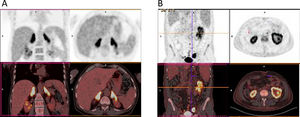

On cranial magnetic resonance imaging (MRI) (Fig. 1), the findings were (Table 1): multiple lesions in white matter and corpus callosum (some of them with enhancement and others with hemorrhagic foci) and multifocal infarcts with hemorrhagic transformation. Leptomeningeal branch aneurysms were found in patient 3. In two patients with spinal cord syndrome, the spinal cord MRI showed lesions with enhancement. A PET-FDG was performed in five patients showing various areas of elevated uptake in all of them (Fig. 2). Three patients underwent random skin biopsies, which were normal. In patient 1, the diagnosis was made by muscle biopsy. Targeted biopsy after PET-FDG findings was performed in four patients, which allowed the diagnosis of IVL to be established in three. One patient with pathological PET-FDG could not undergo solid organ biopsy because of severe thrombopenia and the diagnosis was established by coxal biopsy. One patient was diagnosed postmortem. In this last patient, a diagnosis was not reached despite pancreatic biopsy due to the fibrohematic content not suitable for analysis, although the suspicion of IVL had already been established during his lifetime.

Resonance imaging findings of two different patients. Patient 5 (top row): multiple hyperintense white matter lesions are shown in FLAIR image (A), with involvement of corpus callosum (arrows). Signs of hemorrhage on the gradient echo sequence (B) and enhancement after gadolinium injection in T1-weighted image (C) are present in some lesions. In dorsal spinal cord, an enhanced lesion is seen in a sagital T1-weighted image (D). Patient 3 (bottom row): A left frontal lesion with mass effect shows heterogeneous contrast enhancement in T1-weighted image (E). Lesion is hipovascular in perfusion sequence (F) and shows diffusion restriction in ADC map (G). Angio-CT image shows a left parietal leptomeningeal aneurism (thick arrow) (H).